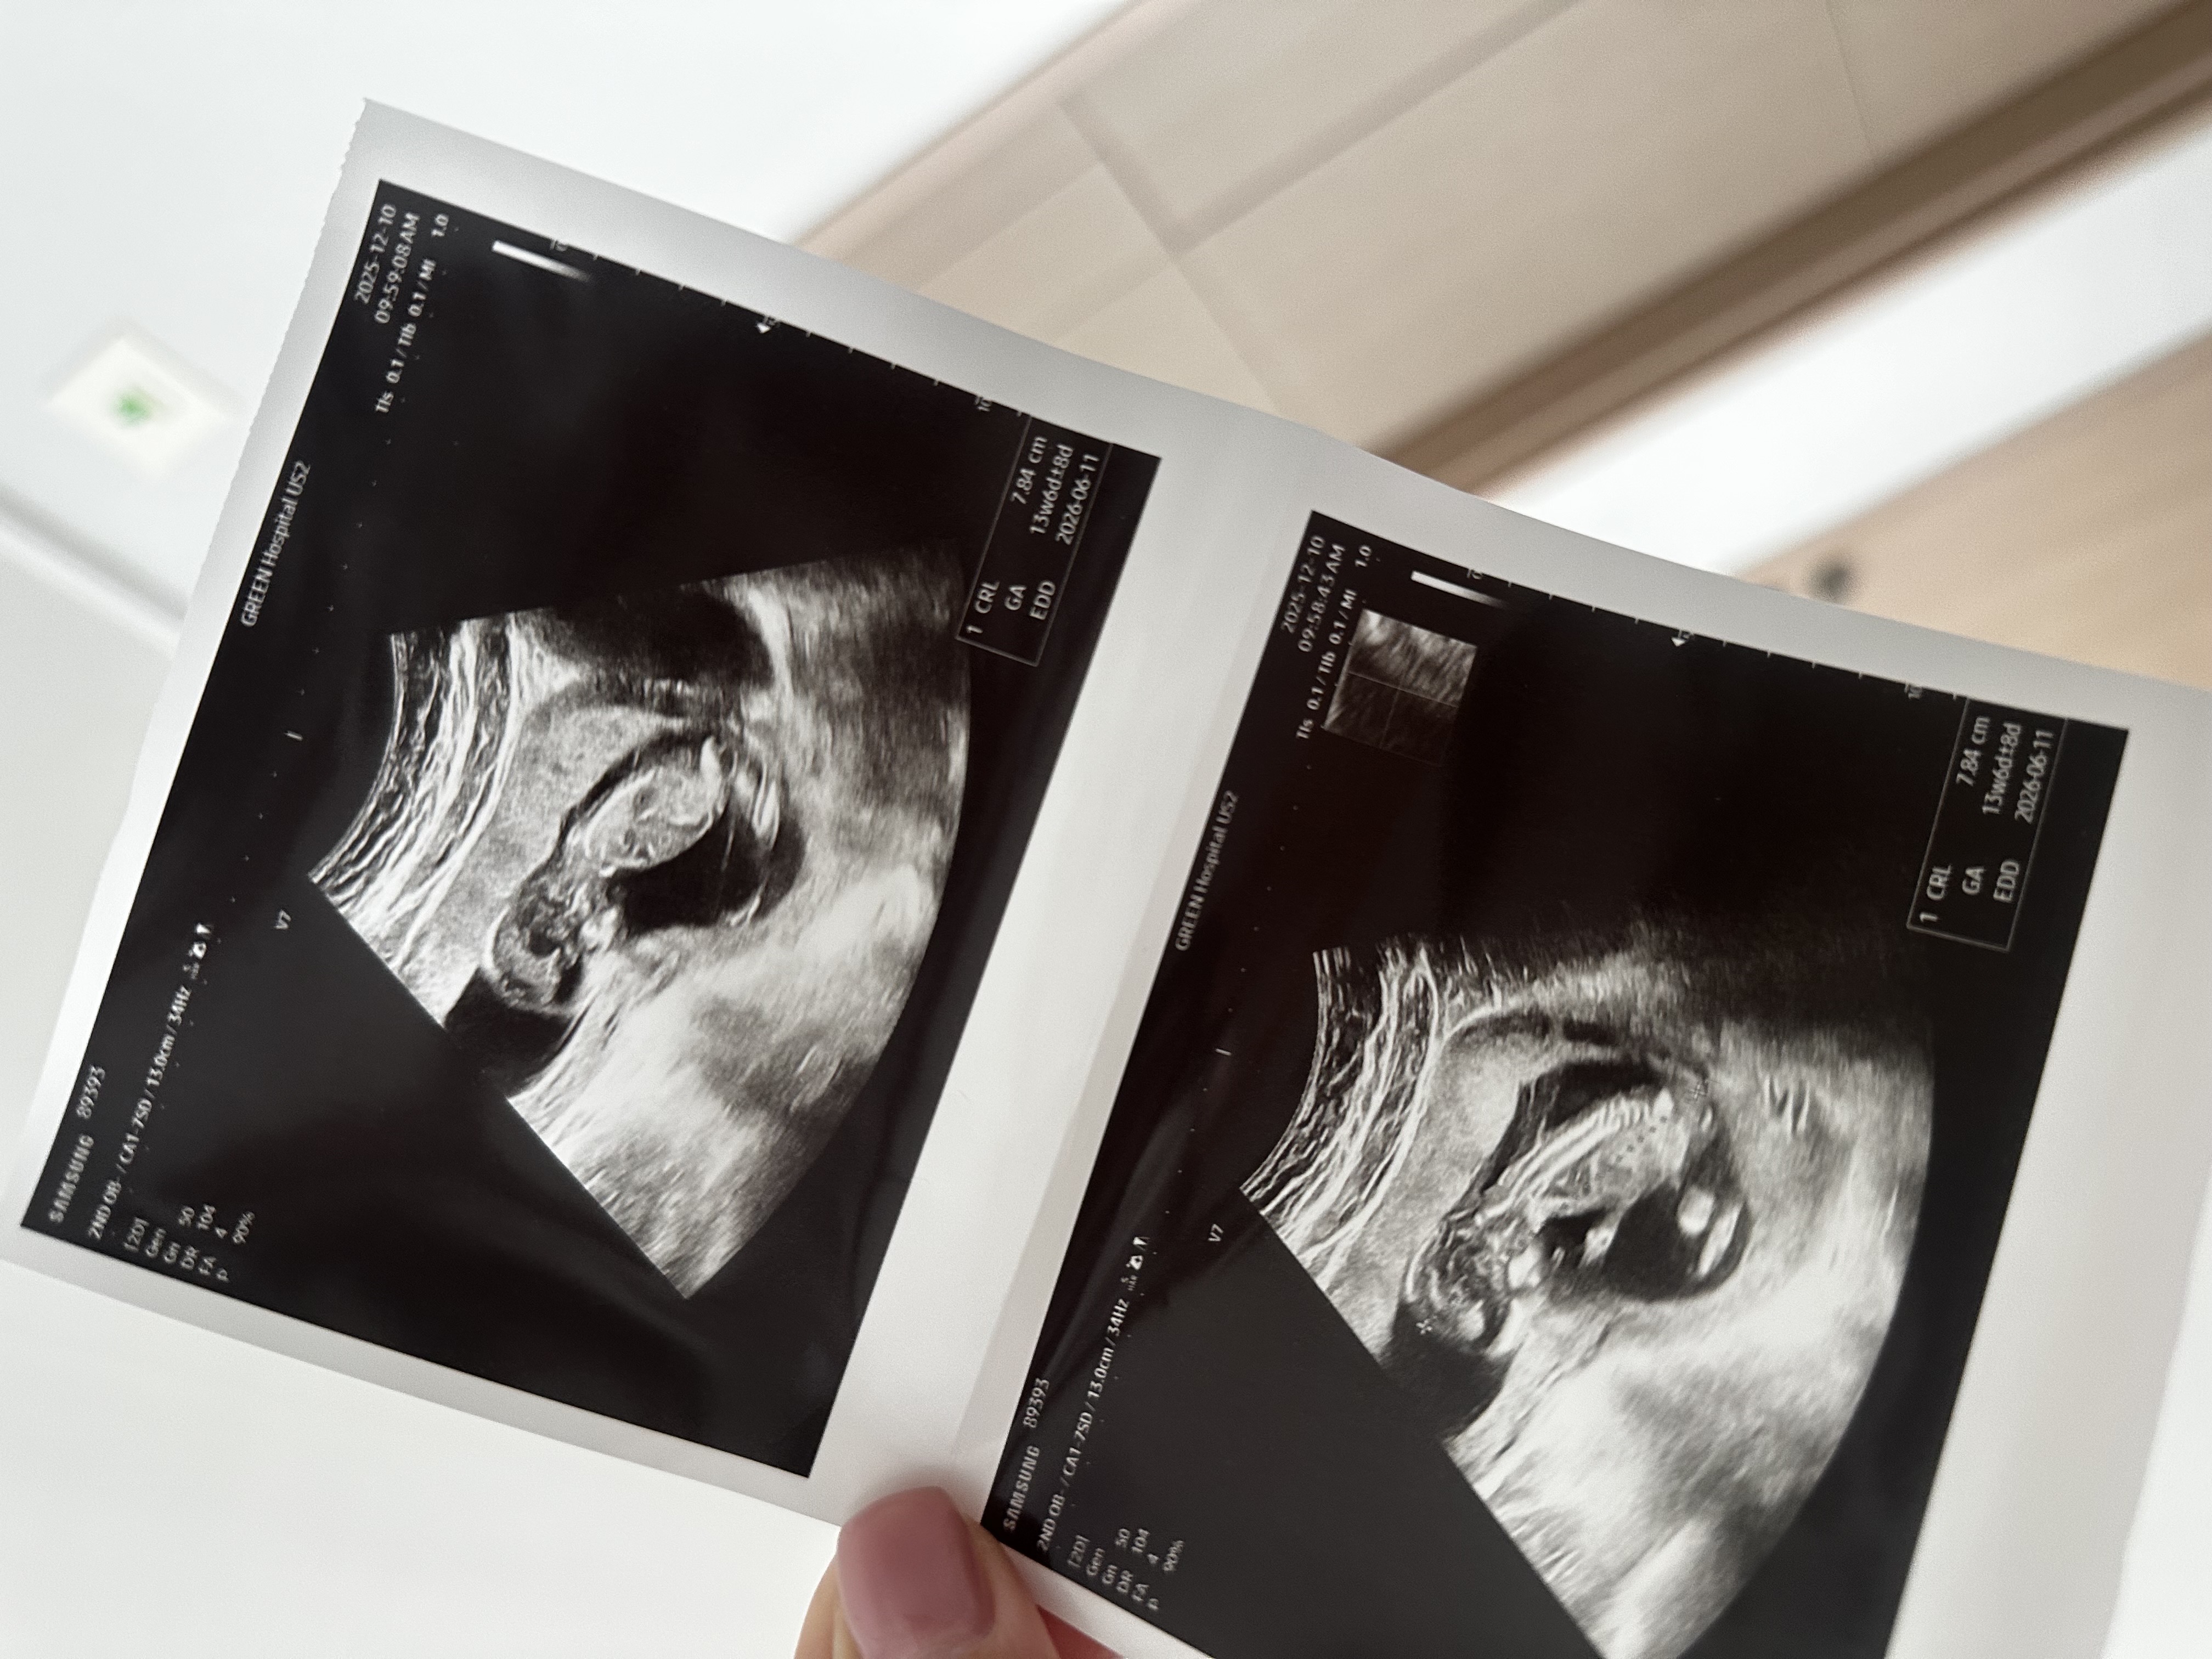

[13주 2일] 성별 추측 부탁드려요

사진에 안보여요